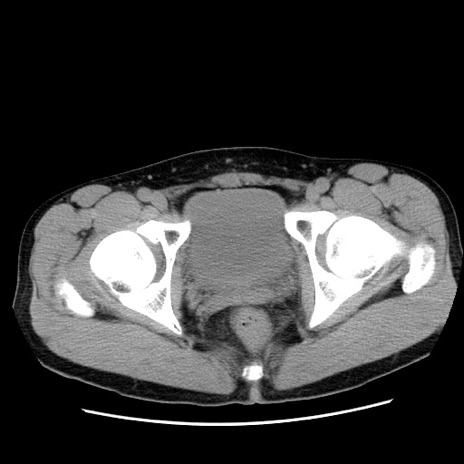

症例36(横断像)

【症例】20歳代 男性

【主訴】心窩部痛

【現病歴】今朝より上腹部痛あり。一旦軽快していたが再度出現したため救急要請。昨日夕に白身の魚を含む刺身を食べた。

【身体所見】BP 136/89mmHg、HR 74/min、BT 37.0℃、腹部:膨満、軟、心窩部に圧痛あり。反跳痛なし、筋性防御なし、腸雑音やや亢進あり。

【データ】WBC 17700、CRP 0.48

冠状断像